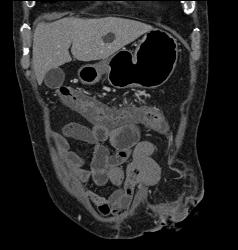

Perforated Appendix With Appendicitis